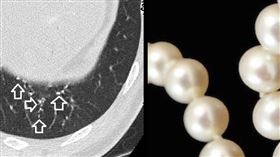

不是肺癌?照出一串珍珠項鍊 醫喊:安啦

衛福部統計,113年癌症死亡人數為5萬4032人,每...

2025/08/26 07:47